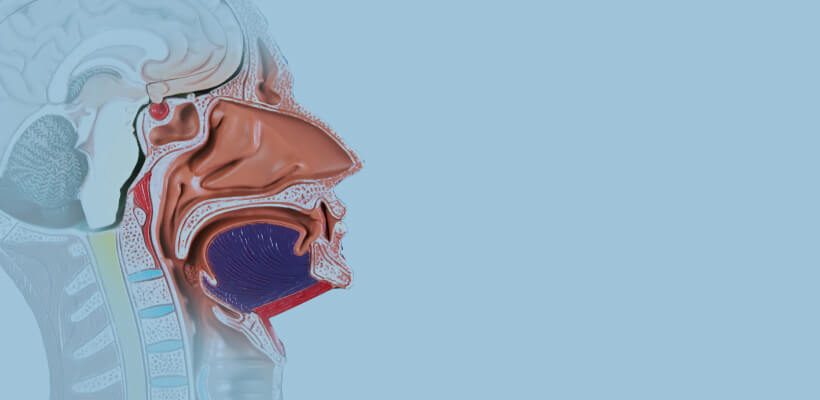

Non-Vascular IVR

Products